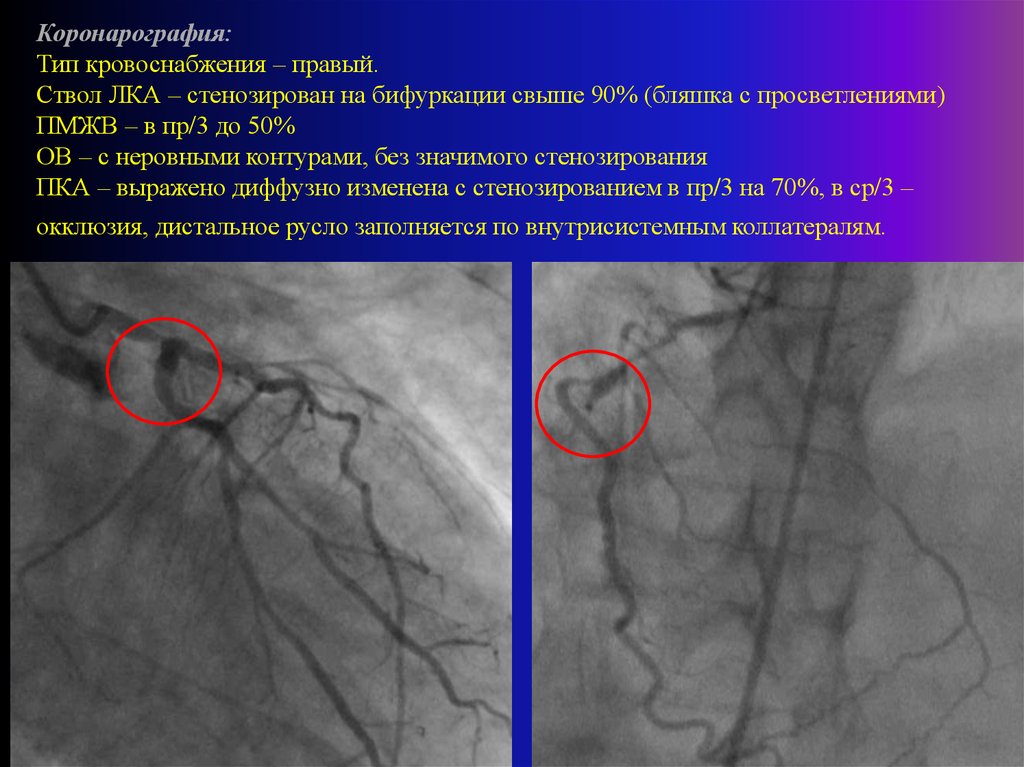

Хроническая окклюзия артерий: причины, симптомы и лечение